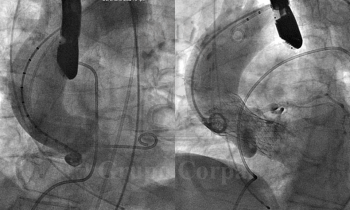

Imágenes antes y después de implante de prótesis aórtica

Blog Cardiológico   Imágenes angiográficas y ultrasónicas de paciente con estenosis aórtica tras implante de CoreValve Imágenes hemodinámicas y angiográficas antes y después del implante percutáneo de una prótesis...

CoreValve Cruz Roja Nov/17 Nuevo implante percutáneo de válvula aórtica en Hospital Cruz Roja (@HospitalCRCordoba). Aortografía basal. 2. Inicio del implante. 3. Implante completado. 4. Aortografía...